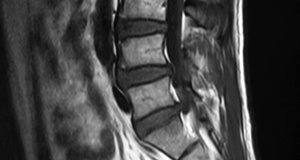

The "real estate" of a space-occupying lesion in the form of a herniated or bulging disc (degeneration or from alteration of motion segment integrity) is the region between the disc and the neurological element. If there is adequate space evidenced by cerebral spinal fluid, the likelihood of your patient responding favorably to chiropractic care is much greater.

In triaging the care of your patient, you also must identify if the disc is causing an abutment of the root or cord, or a compression. An abutment is when you have only one side of the neural element making contact; usually the disc on the anterior component of the cord or the nerve root. With an abutment, you have much more leeway, as there is adequate space on the opposing side, while compressions give you little room to work with.